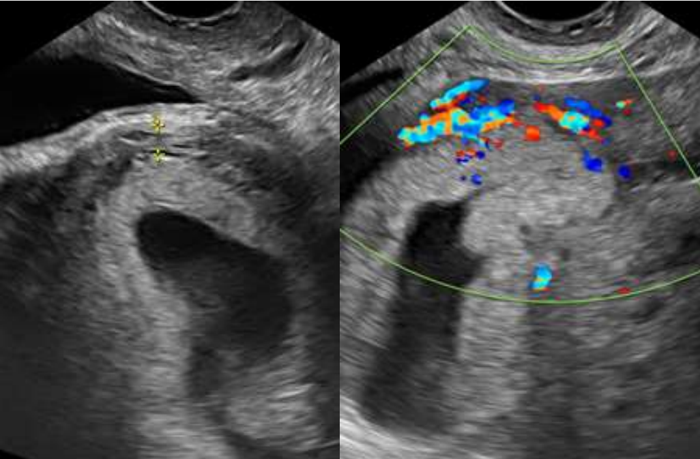

Paciente, 32 anos, secundigesta (cesariana anterior), na 6ª semana de gravidez com queixa de sangramento genital há 20 dias, com piora há 12 horas. Ao exame encontrava-se com estado geral bom, hipocorada (+/4+), acianótica, consciente e orientada. Pressão arterial de 120 x 80 mmHg. Frequência cardíaca de 98 bpm. Abdome plano depressível e indolor, sem massas palpáveis e ausência de sinais de irritação peritoneal.

Submetida a exame ultrassonográfico transvaginal com a imagem abaixo, revelando saco gestacional dentro de cavidade uterina, de contorno regular, em topografia de istmocele.

Assinale a alternativa a qual sugere possível complicações relacionada a principal diagnóstica: